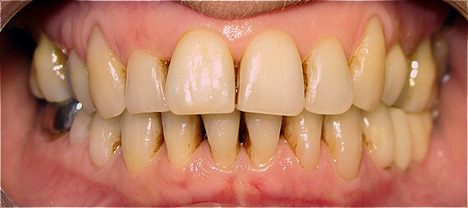

Resultado de colocação de implante dentário na Clínica São Filinto

A colocação de implantes dentários de titânio é, atualmente, a melhor forma de substituir os dentes ausentes, pois não só lhe devolve a estética dentária perdida, como também a sua função mastigatória.

A utilização de novos materiais nas coroas implanto-suportadas, como o zircónio, e as novas técnicas laboratoriais avançadas, em conjunto com a utilização de softwares especializados na construção das coroas dentárias, aumenta ainda mais a estética dentária porque confere ao dente um aspeto muito natural.